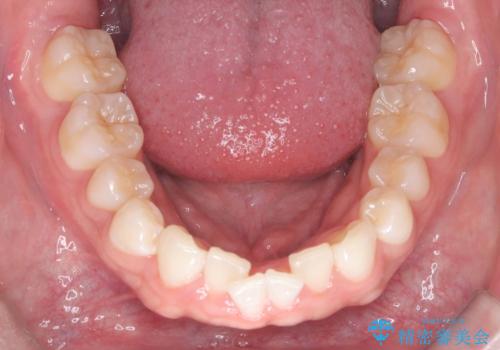

歯のデコボコを治したい|インビザラインで綺麗な歯並びに!|矯正期間は6ヵ月!

- 歯のデコボコが気になるを主訴に来院された患者様です。

インビザラインで歯は抜かずに非抜歯でデコボコを改善しました。

インビザラインで叢生の改善を行いました。

歯は抜かずに、拡大と少しのIPRで並べました。

矯正期間は半年です。

綺麗な歯並びを手に入れ大変ご満足していただきました。